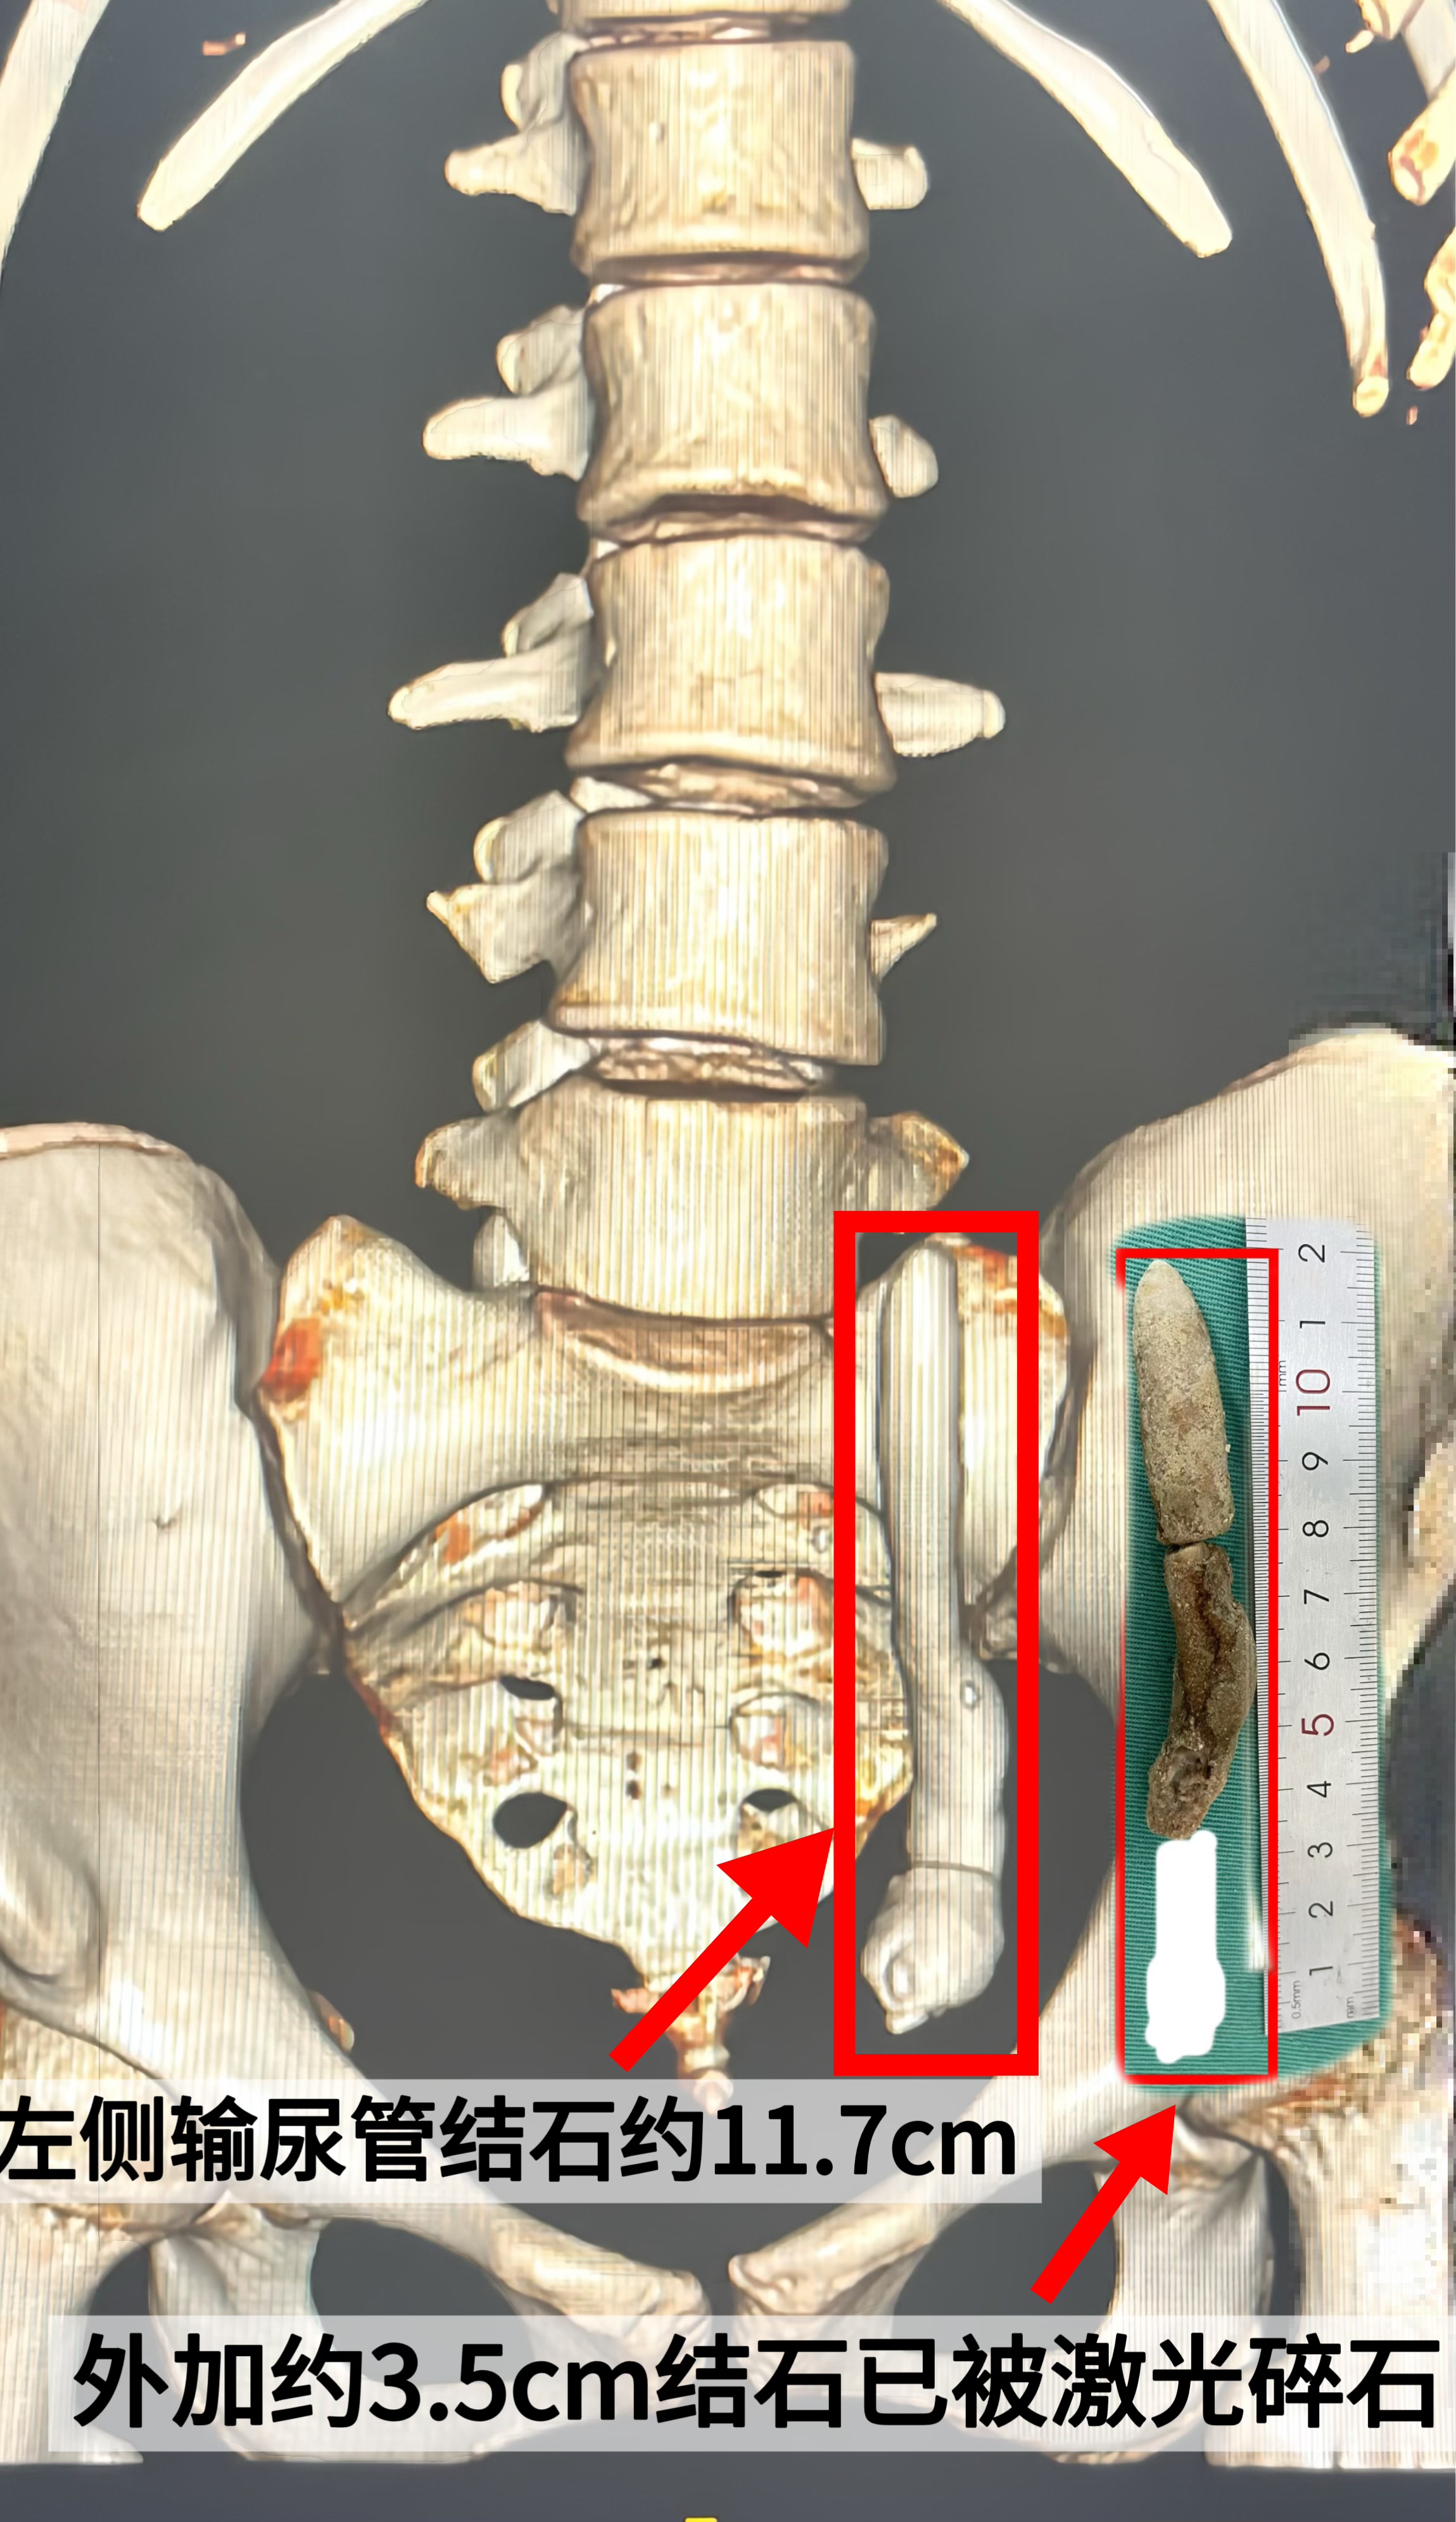

近日,16岁的林女士突然感觉左侧腰部持续疼痛,遂与家属一同前往永泰圣德医院就诊。经医院门诊评估,她被诊断为“输尿管结石”。检查显示,林女士的左侧输尿管下段结石117mm×14mm、CT值约800Hu。

考虑到以上状况,医疗团队创新提出“双镜联合”技术碎石手术方案,即结合经腹腔镜辅助输尿管切开取石与经尿道输尿管镜钬激光碎石两种先进技术一次性清除结石,不仅显著提升了碎石与清石效率,有效缩短了手术时长,更在减少手术创伤方面展现出卓越优势,为患者的疾病治疗及整体预后带来了积极影响。

在永泰圣德医院外科副主任医师尤财生和泌尿外科主治医师林励生的带领下,手术顺利进行,全程耗时约120分钟。林女士体内的结石被完全清除,目前已康复出院。